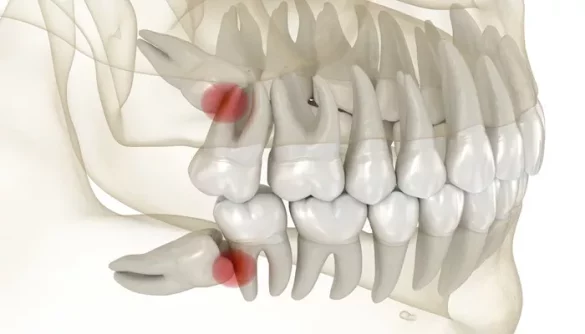

Wisdom teeth, the third set of molars located at the back of your mouth, typically emerge in late adolescence or early adulthood. For many, this eruption brings about pain, swelling, and potential complications that require extraction.

The removal of wisdom teeth is one of the most common dental procedures, especially for individuals between the ages of 17 and 25. Although it is a routine surgery, the recovery process can be somewhat challenging. Understanding the stages of healing and what to expect during each phase can make the process smoother and less stressful.